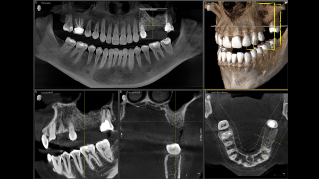

Galería de muestra de imágenes panorámicas 3D

11 cm x 10 cm implant case

8 cm x 8 cm implant case

La tecnología 3D se está estableciendo cada vez más en los consultorios dentales en todo el mundo. Para diagnósticos más precisos y explicaciones del tratamiento, los rayos X en 3D ofrecen varias ventajas. Ya sea para dientes superpuestos, recorridos inesperados de los canales de los nervios, raíces ocultas o anomalías de las articulaciones temporomandibulares, las imágenes en 3D tienen un valor inestimable para un gran número de diagnósticos.

Orthophos SL 3D ofrece una gran variedad de opciones para satisfacer estas necesidades: diferentes tamaños de volumen donde elegir, modos HD/SD/Dosis bajas de radiación y un software inteligente e intuitivo para aprovechar al máximo las imágenes obtenidas y vincularlas directamente al tratamiento.